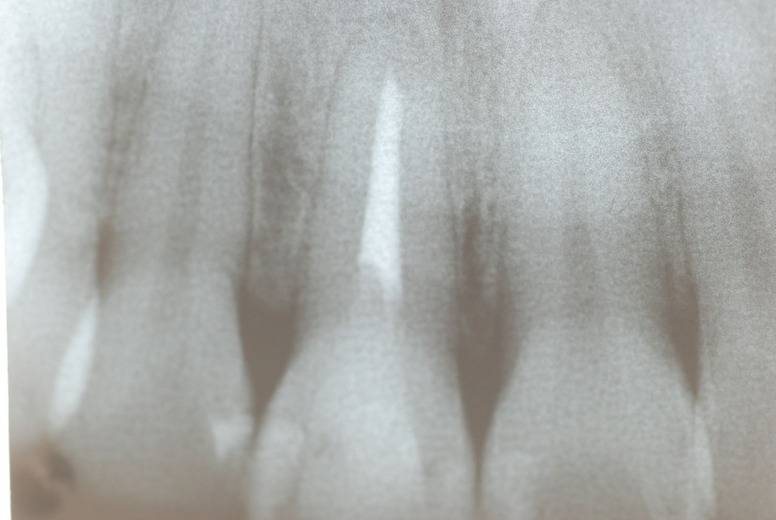

入れ歯の話から入りました。色々不満で注文があるようです。でも話が一段落して口腔内を調べると殆どの歯が重症で抜けそうな歯だらけなのです。

なぜ病気になるのかわからない方が多すぎます。歯が抜けるのは病気だからです。病気を治さずに何かお口の中に入れても土台である歯が抜けてしまっては同じことなのです。